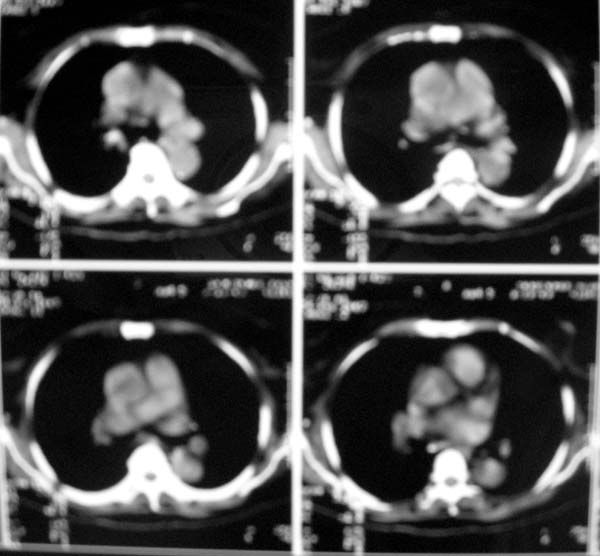

以下是引用zjzjr在2007-8-30 22:22:00的发言:[br]右上肺肺囊肿合并感染.右下肺肺大泡.左肺舌段感染.

以下是引用天南地北在2007-8-30 23:19:00的发言:[br][quote]以下是引用zjzjr在2007-8-30 22:22:00的发言:[br]右上肺肺囊肿合并感染.右下肺肺大泡.左肺舌段感染.